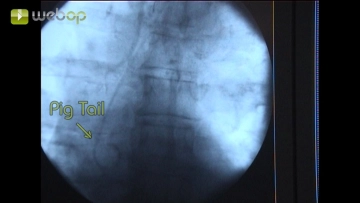

Después de la introducción de la prótesis aórtica endoluminal relativamente rígida junto con el sistema portador, las marcaciones pueden ocasionalmente desviarse de la posición real de los marcadores. En distancias estrechas entre el extremo de la prótesis y la arteria subclavia o el tronco celíaco, como en el ejemplo de la película, se requiere una DSA renovada antes de la liberación del cuerpo de la prótesis, para que los lúmenes de los vasos mencionados no se obstruyan accidentalmente.